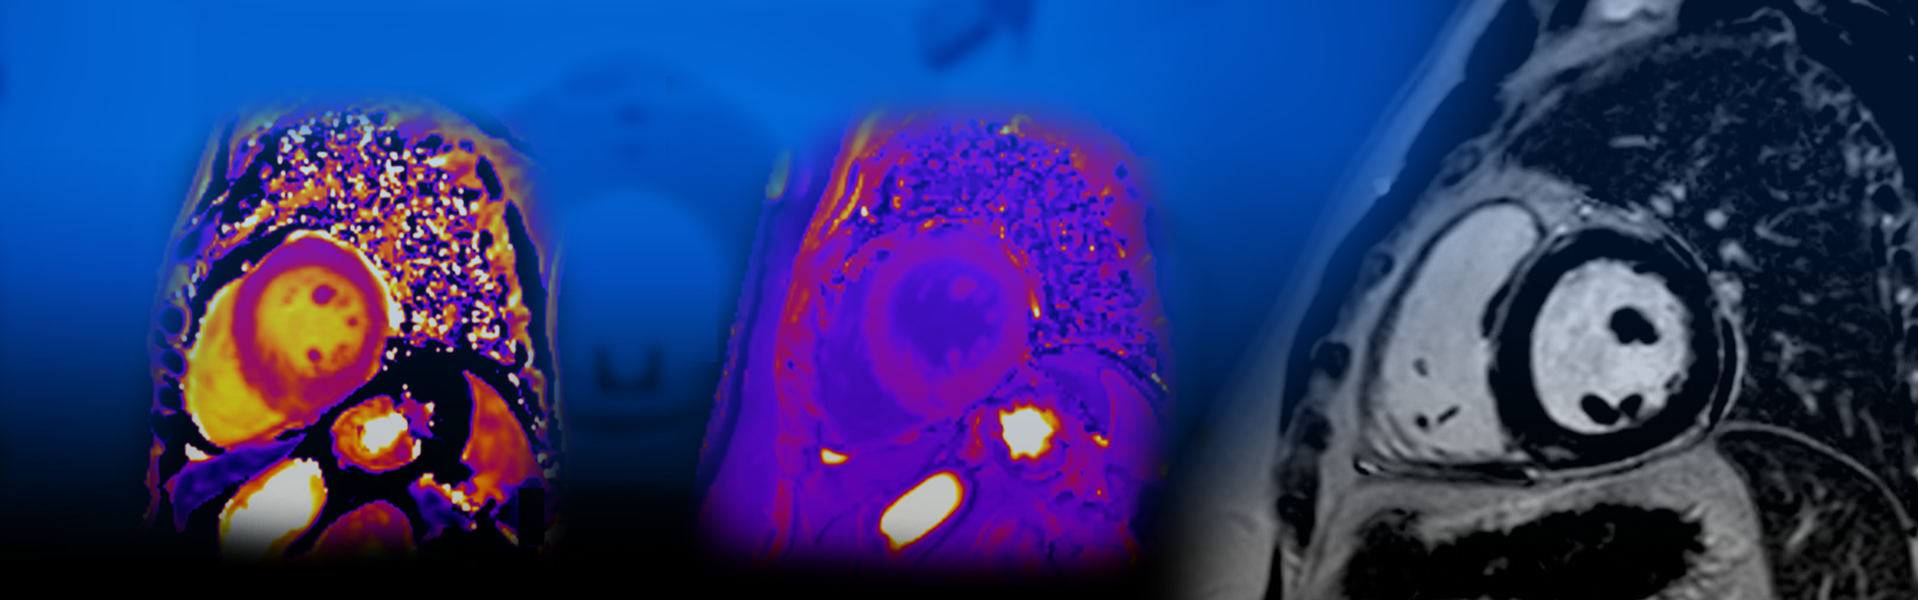

Ο καρδιολόγος Δημήτριος Μαραγιάννης, με εξειδίκευση στην εφαρμογή των μεθόδων της Yπερηχοκαρδιογραφίας και της Mαγνητικής Tομογραφίας Kαρδιάς για την ανίχνευση των καρδιαγγειακών παθήσεων, σας καλωσορίζει στο ιατρείο Athens Premier Cardiology.